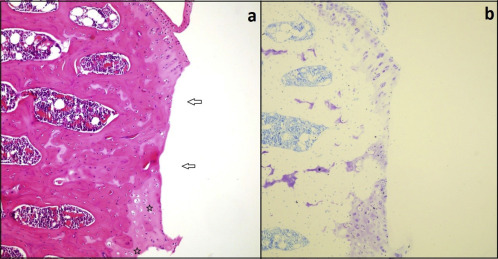

Fig. 3

Fig. 3.

Images from Group 1 (saline-treated knees) (a) Extensive loss of the transitional and radial zone (arrows) as well as hypocellularity in the residual chondroid structure (asterisk) and cell deaths. (b) Prominent loss of proteoglycan matrix manifesting as pale areas in Toluidine blue staining.

Statistically significant differences were found between the control group (11 left knees) and papain-injected group (11 right knees) regarding total Mankin scores (control: 3.91, papain: 14.0; p < 0.001) (Table 1 ). Representative histological lesions in the cartilage of OA-induced rats were; moderate and severe surface irregularities, cleft formation in the transitional and radial zone, hypercellularity and disrupted columns of chondrocytes and multilayered tidemark. On the 63rd day, lesions were not reduced and got worse in Group 1. Representative histological lesions in Group 1 were; loss of severe matrix loss, moderate pannus formation, all of the above and large patches of cell death and sloughing of layers till mid-zone (Fig. 2  ;  Fig. 3 ). On the 63rd day, there was a statistically significant difference between Group 1 and Group 2, between Group 1 and Group 3 regarding total Mankin scores (Group 1: 20.27, Group 2: 10.2, Group 3: 7.18) (Fig. 4  ;  Fig. 5 ). Group 3 showed statistically significant improvement in terms of the proteoglycan content of matrix when compared to Group 2 (p < 0.05). Descriptive histological lesions with scores are presented in Table 2  ;  Table 3 .